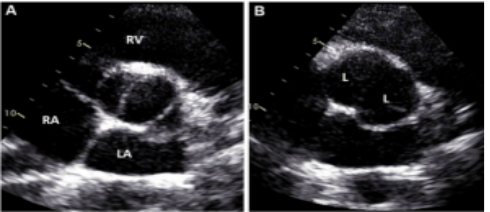

最新国际共识认为仅基于外科角度的Sievers分型仍有局限性,因此新的分型为:融合型、双窦型和部分融合型。其中融合型最常见,占90%~95%,相当于TypeⅠ型。双窦型BAV并不常见,占5%~7%,由大小、形状大致相同的两个瓣叶构成,分前侧对侧表型和前后表型(图b)。部分融合型的流行率尚不清楚,表现为典型的三叶瓣膜,但在连合底部可见<50%的瓣尖融合。至于Sievers分型中的Type Ⅱ型,共识认为称单叶瓣较为合适。

双窦型